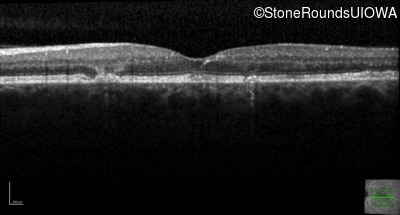

Optical Coherence Tomography - Right - 20/20 -1 sc

Exemplar / OCT Stack